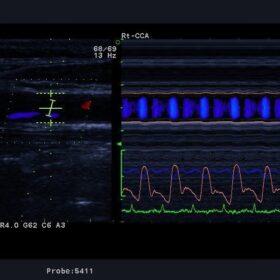

Ultrasound Aloka Prosound Alpha 10 – Image Gallery and Videos

- Thanks to Precise Delay Timing Control, the accuracy of reception/transmission delay is four to eight times higher than conventional systems, providing high-resolution beams.

Aloka UST-5411 Vascular Linear

Aloka UST-5412 Vascular Linear

Aloka UST-567 Vascular Linear